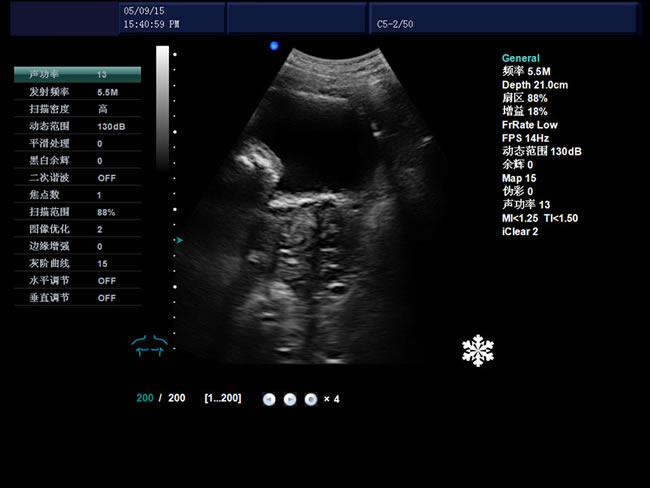

S9 彩色多普勒獸用超聲診斷儀

• S9彩色多普勒獸用超聲診斷儀是徐州市大為電子設備有限公司推出的一款全新的彩色超聲診斷儀器。

高集成數字式彩色多普勒技術

寬頻探頭,頻率范圍從2.0MHz到10.0MHz

強勁的組合式模塊化軟件設計

全數字式大容量圖像存貯和文件歸檔管理

適用范圍

適用于犬、牛、羊、馬、貓、豬、海豚、駱駝等。